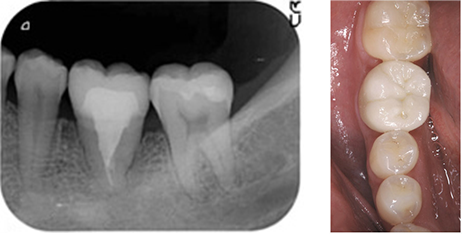

過去に抜歯と言われ インプラントを薦められた38歳女性の患者

BEFORE

向かって左から3番目の大きな歯が割れており、抜歯を余儀なくされました。

レントゲンです。 割れた歯の周囲の骨が感染により溶けて黒くなっています。向かって最右が移植する親知らずです。

AFTER

感染が大きかったことから割れた歯を抜歯後4週を待って同測の親知らずを移植し、約2ヵ月後にセラミック製のクラウンを被せました。 根の治療が済み、レントゲンは術後3年のものですが、異常なく安定しているのがわかります。